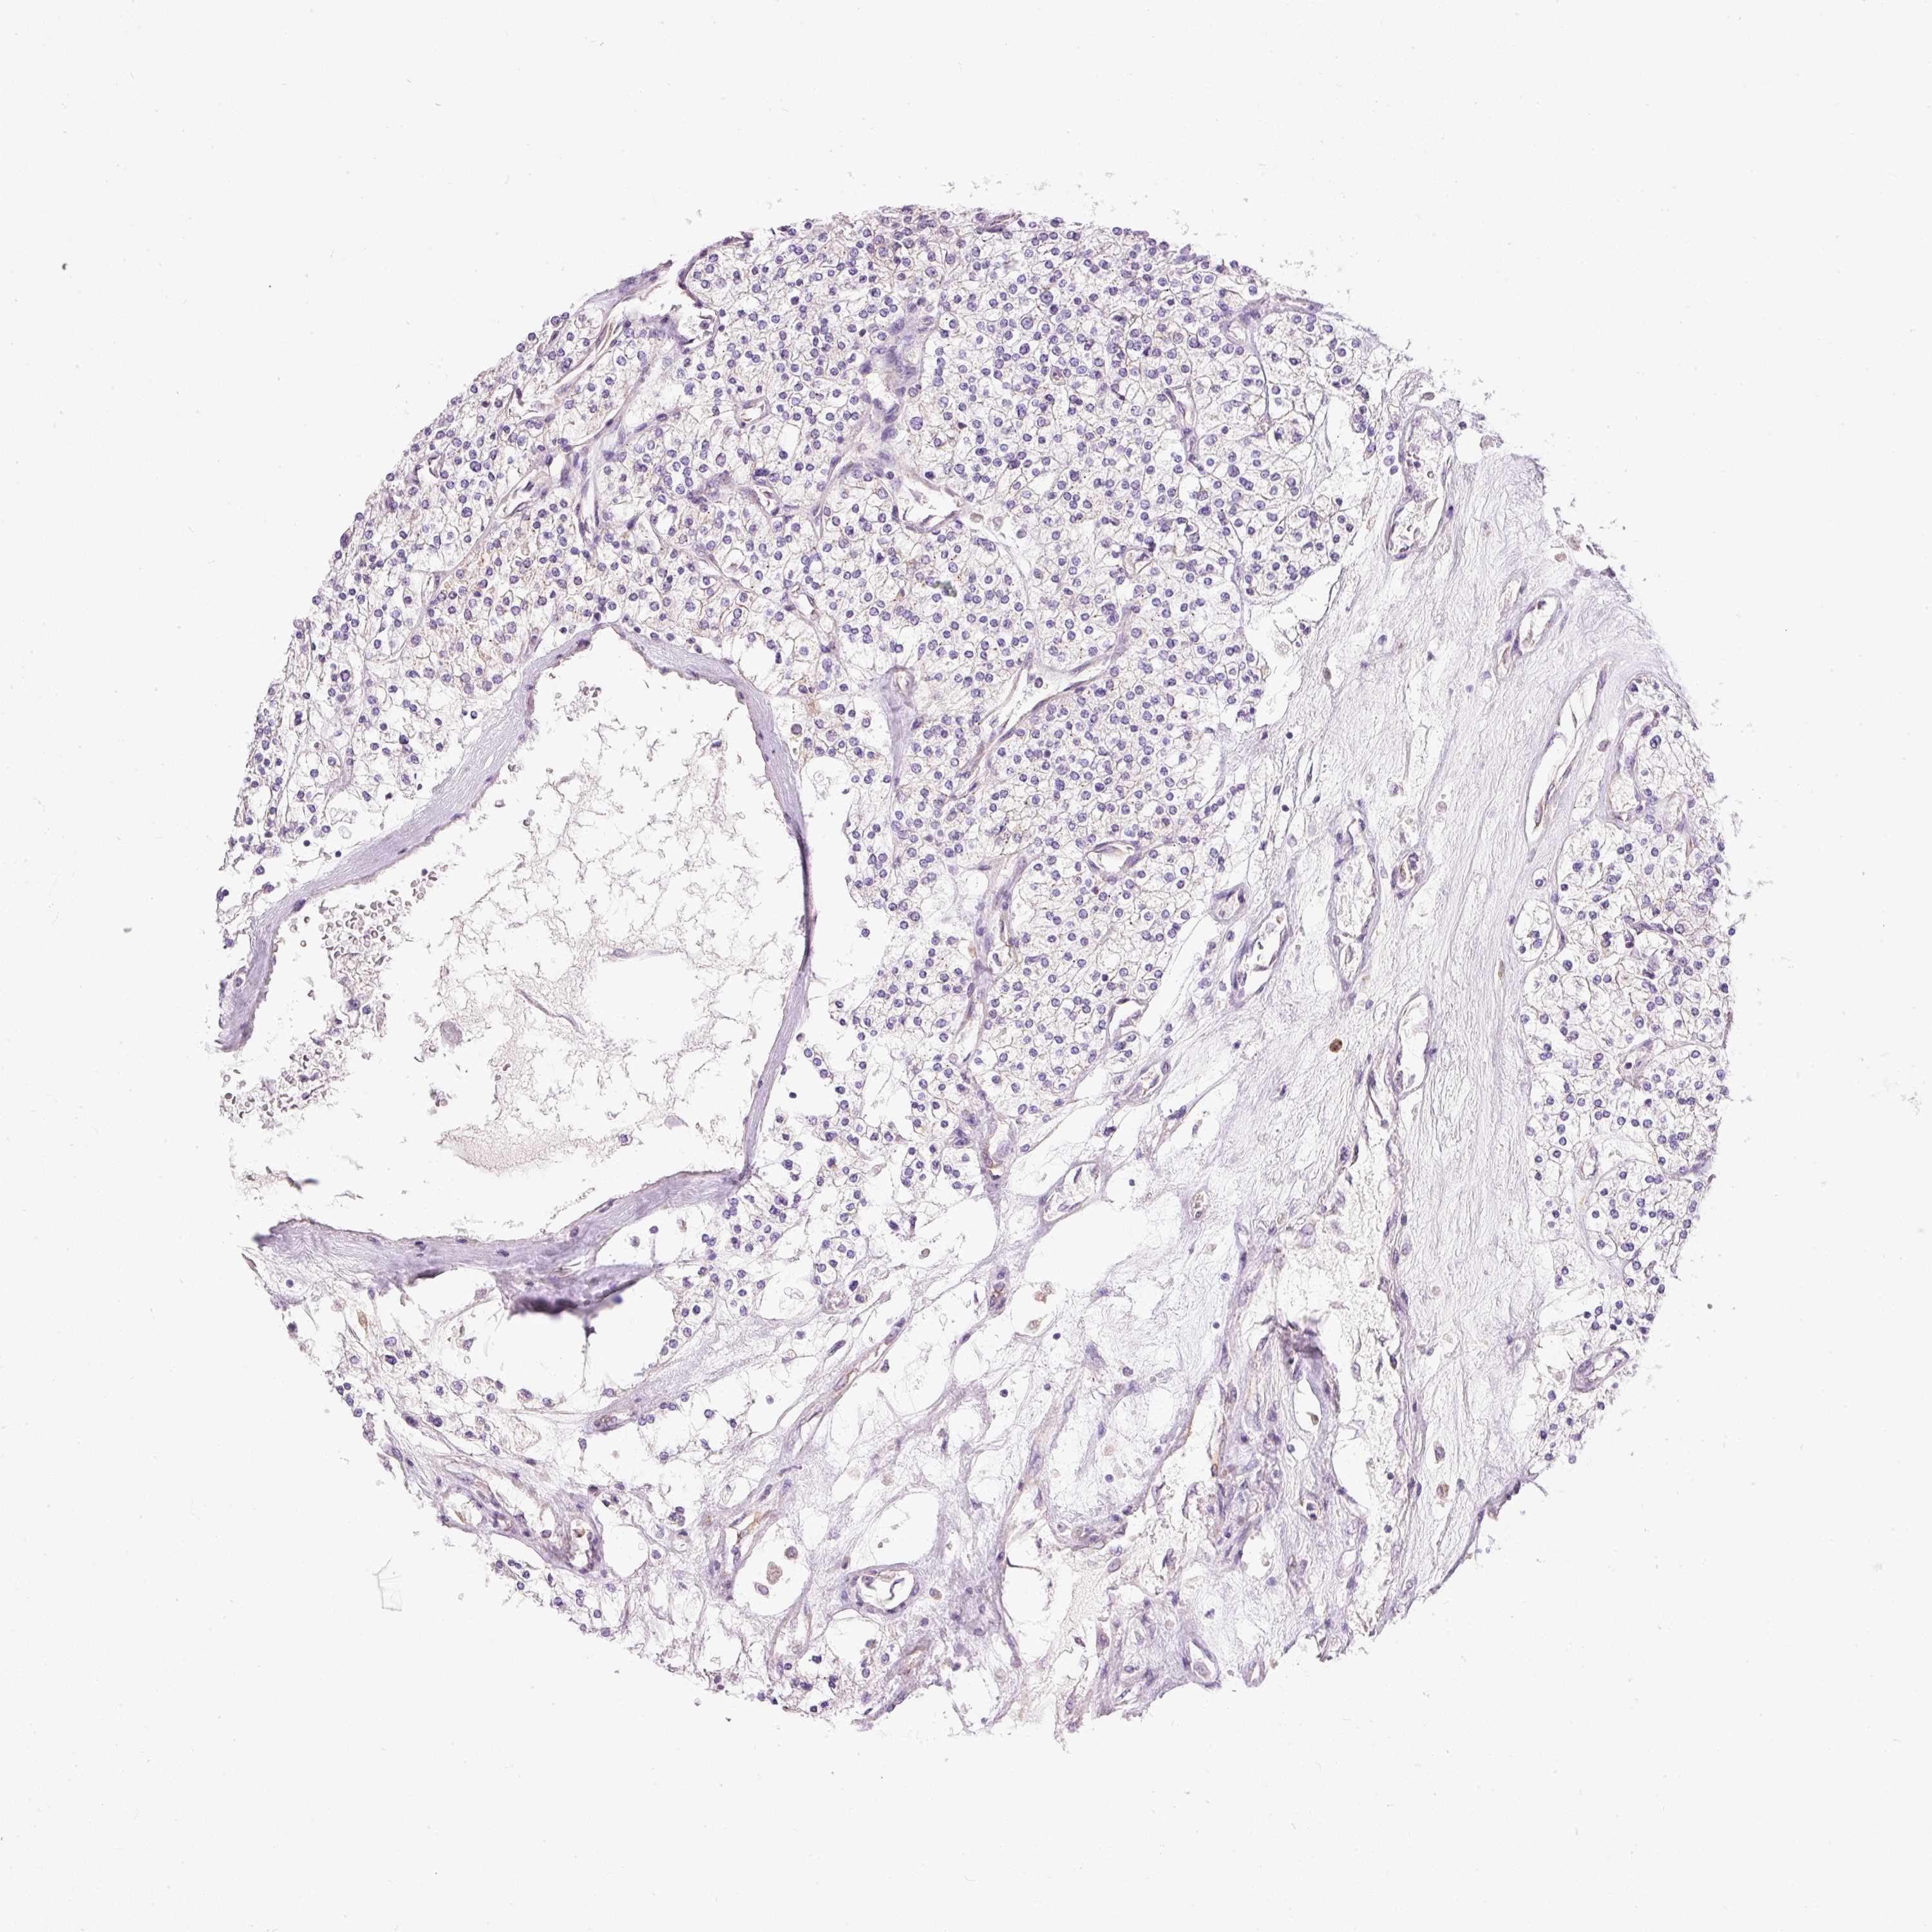

KIDNEY RENAL PAPILLARY CELL CARCINOMA (TCGA) - Interactive survival scatter ploti

The Survival Scatter plot shows the clinical status (i.e. dead or alive) for all individuals in the patient cohort, based on the same data that underlies the corresponding Kaplan-Meier plots. Patients that are alive at last time for follow-up are shown in blue and patients who have died during the study are shown in red.

The x-axis shows the expression levels (FPKM) of the investigated gene in the tumor tissue at the time of diagnosis. The y-axis shows the follow-up time after diagnosis (years). Both axes are complimented with kernel density curves demonstrating the data density over the axes. The top density plot shows the expression levels (FPKM) distribution among dead (red) and alive patients (blue). The right density plot shows the data density of the survived years of dead patients with high and low expression levels respectively, stratified using the cutoff indicated by the vertical dashed line through the Survival Scatter plot. This cutoff is automatically defined based on the FPKM cutoff that minimizes the p-score. The cutoff can be changed by dragging the vertical line or by entering a cutoff value in the square labeled "Current cut-off".

Under the Survival Scatter plot the p-score landscape (black curve; left axis) is shown together with dead median separation (red curve; right axis). Dead median separation is the difference in median mRNA expression between patients who have died with high and low expression, respectively. It is calculated as follows: median FPKM expression of dead patients with high expression - median FPKM expression of dead patients with low expression. This is intended to aid the user in visually exploring custom cutoffs and the associated p-scores and dead median separation.

Individual patient data is displayed and can be filtered by clicking on one or more of the category buttons on the top of the page. Categories describing expression level and patient information include: high, low, alive, dead, female, male and tumor stages. The scale of the x-axis can be toggled between linear and log-scale by clicking on the "x log" button. Mouse-over function shows TCGA ID, patient information and mRNA expression (FPKM) for each patient.

& Survival analysisi

Kaplan-Meier plots summarize results from analysis of correlation between mRNA expression level and patient survival. Patients were divided based on level of expression into one of the two groups "low" (under cut off) or "high" (over cut off). X-axis shows time for survival (years) and y-axis shows the probability of survival, where 1.0 corresponds to 100 percent.

PNPLA5 is not prognostic in Kidney Renal Papillary Cell Carcinoma (TCGA)